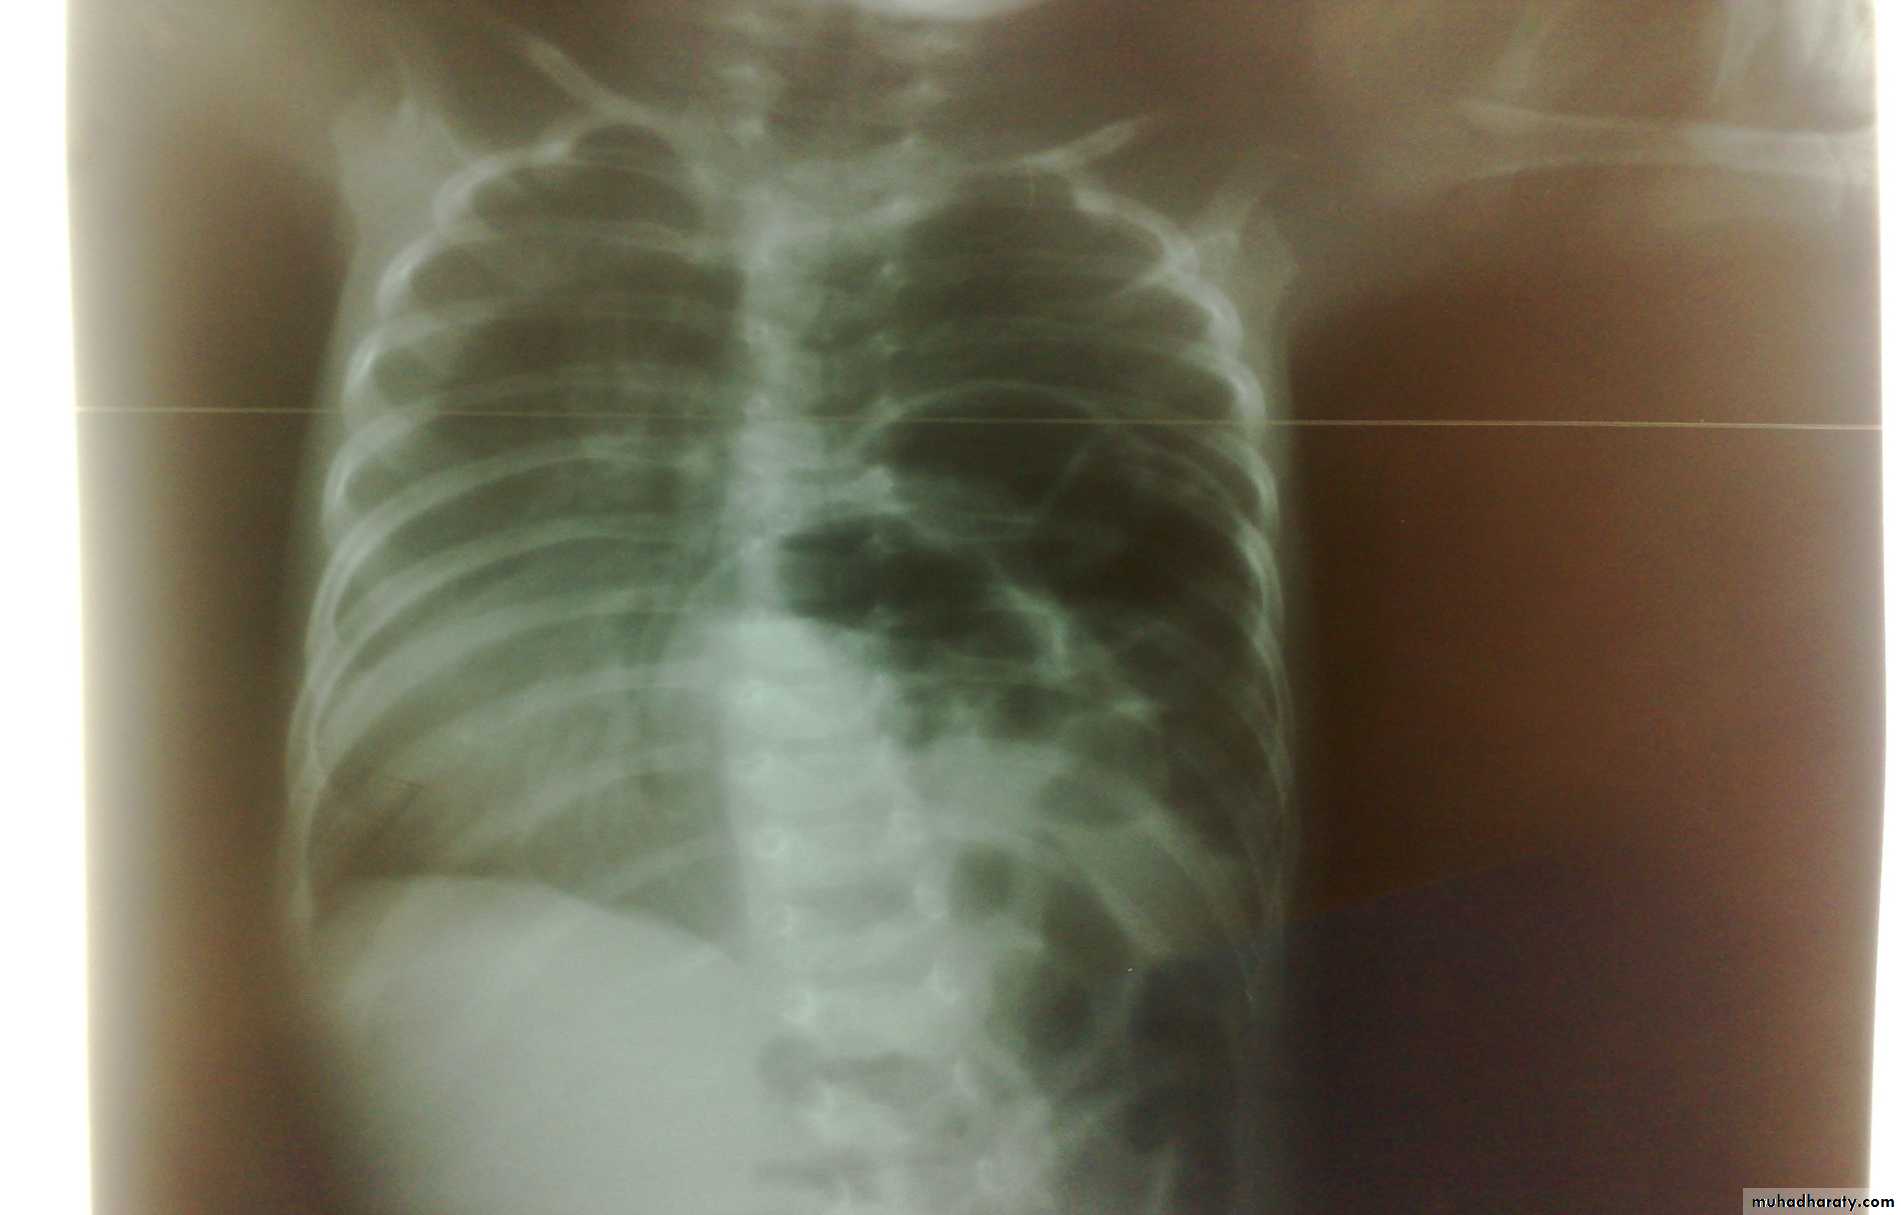

Oesophageal Atresia and Tracheo-Oesophageal Fistula,